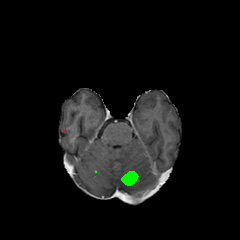

Objectives: This work aims to explore the impact of multicenter data heterogeneity on deep learning brain metastases (BM) autosegmentation performance, and assess the efficacy of an incremental transfer learning technique, namely learning without forgetting (LWF), to improve model generalizability without sharing raw data. Materials and methods: A total of six BM datasets from University Hospital Erlangen (UKER), University Hospital Zurich (USZ), Stanford, UCSF, NYU and BraTS Challenge 2023 on BM segmentation were used for this evaluation. First, the multicenter performance of a convolutional neural network (DeepMedic) for BM autosegmentation was established for exclusive single-center training and for training on pooled data, respectively. Subsequently bilateral collaboration was evaluated, where a UKER pretrained model is shared to another center for further training using transfer learning (TL) either with or without LWF. Results: For single-center training, average F1 scores of BM detection range from 0.625 (NYU) to 0.876 (UKER) on respective single-center test data. Mixed multicenter training notably improves F1 scores at Stanford and NYU, with negligible improvement at other centers. When the UKER pretrained model is applied to USZ, LWF achieves a higher average F1 score (0.839) than naive TL (0.570) and single-center training (0.688) on combined UKER and USZ test data. Naive TL improves sensitivity and contouring accuracy, but compromises precision. Conversely, LWF demonstrates commendable sensitivity, precision and contouring accuracy. When applied to Stanford, similar performance was observed. Conclusion: Data heterogeneity results in varying performance in BM autosegmentation, posing challenges to model generalizability. LWF is a promising approach to peer-to-peer privacy-preserving model training.